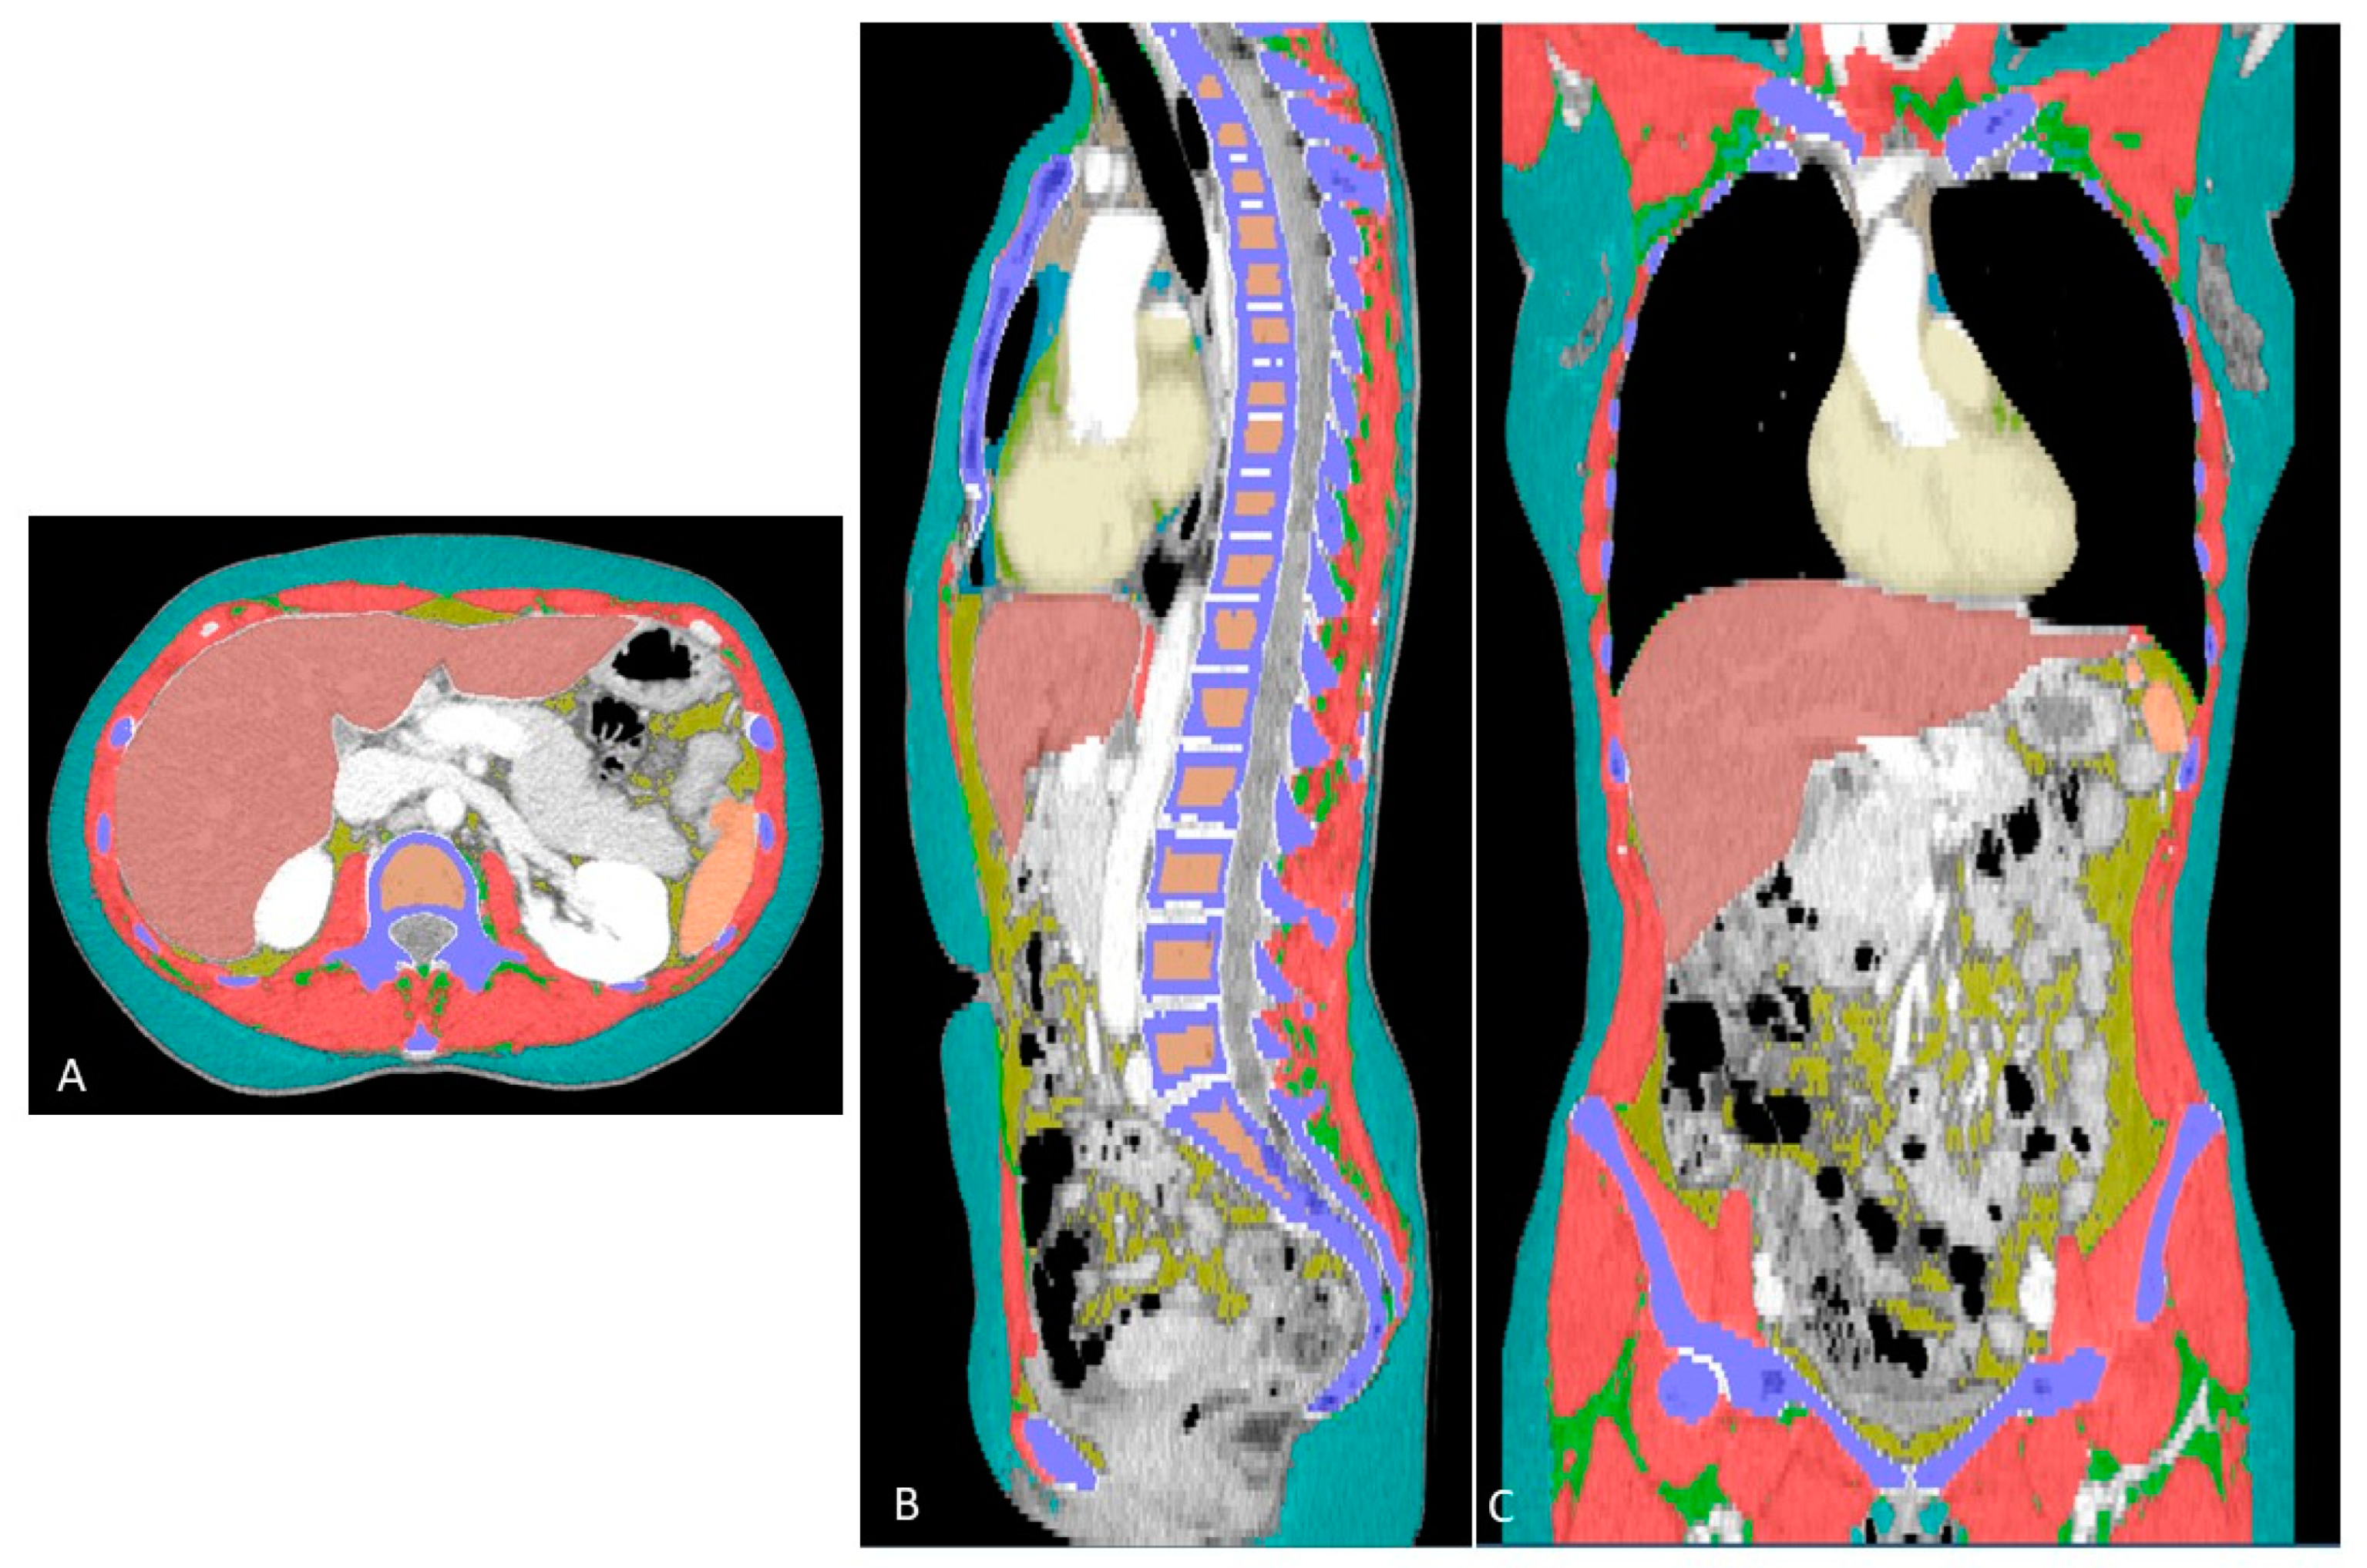

2.3. Extraction of Whole-Body Composition Features